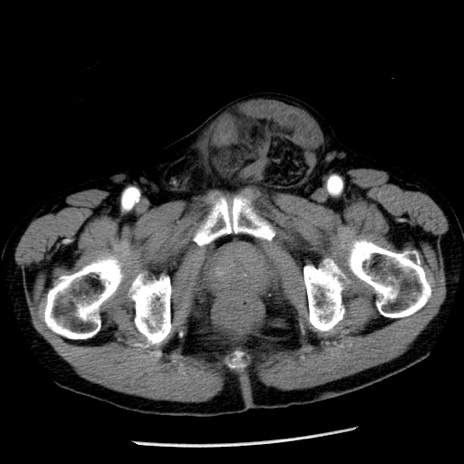

症例26(横断像)

【症例】80歳代男性

【主訴】嘔吐

【現病歴】昨晩2回嘔吐あり、今朝になっても嘔吐あり。来院。

【既往歴】胃潰瘍

【身体所見】意識清明、BT 37.6℃、BP 166/95mmHg、HR 100bpm、SpO2 97%、腹部:平坦・軟、腸蠕動音聴取良好、圧痛なし。

【データ】WBC 21900、CRP 1.46